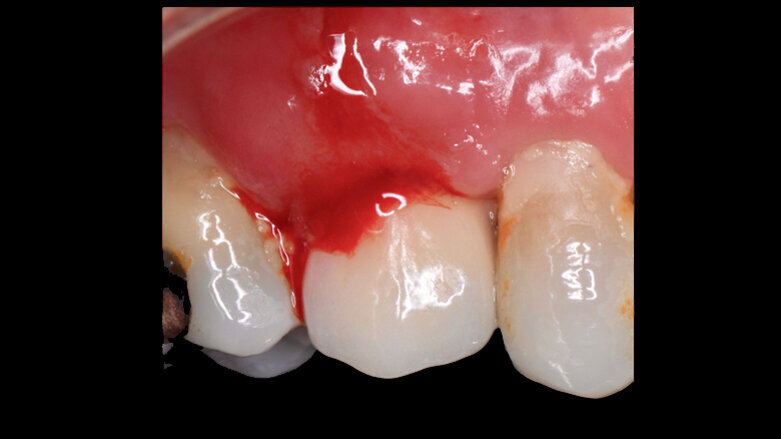

Al control postoperatorio a 30 días la paciente presenta una regeneración de todo el tejido mucoso periimplantar, sellado de tejido blando, color de mucosa normal y no hay  de sangrado. No se realiza sondaje para no afectar la cicatrización (Figura 6).

Figura 6. Control postoperatorio a 30 días presenta una regeneración de todo el tejido mucoso periimplantar, sellado de tejido blando, color de mucosa normal y no hay de sangrado.